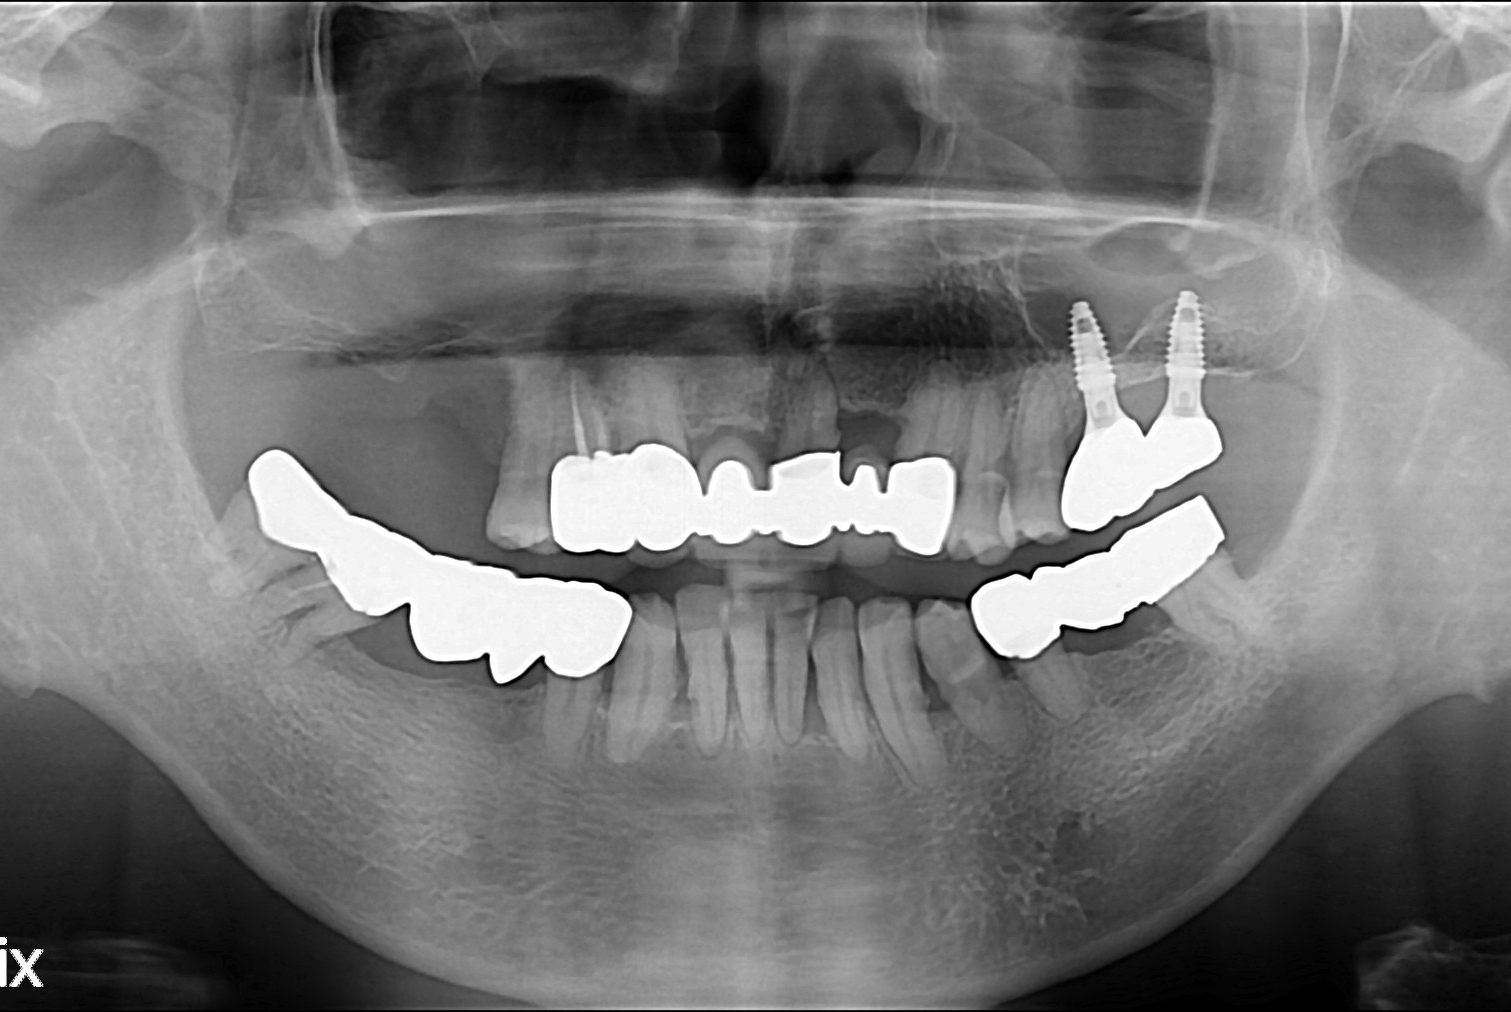

치료전 : 2017-05-25

치료후 : 2017-07-31

세종치과는 많은 환자와 다양한 케이스를 바탕으로 항상 편안한 임플란트 수술을 제공하고자 노력하고,

오래동안 튼튼히 쓸 수 있는 임플란트 수술을 가장 큰 목표로 삼고 있습니다